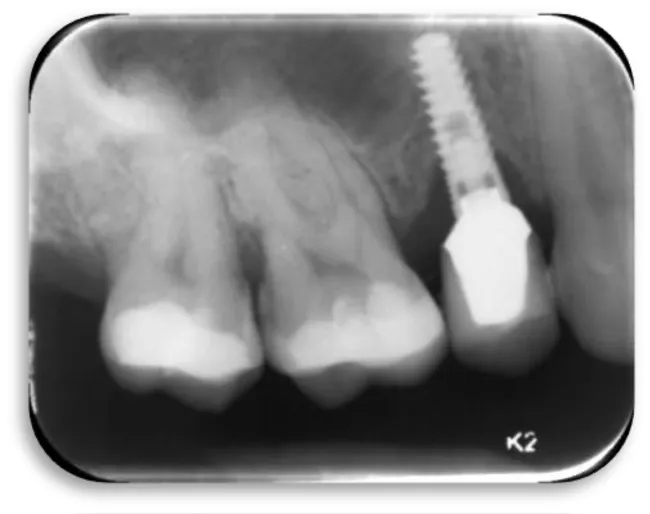

Woman at aged 37 year age, in good health condition and without any systemic diseases, allergic to penicillin came for prosthetic rehabilitation. She was without second premolar and first molar in the lower right quadrant. The patient was provided with dental implants at 45 and 46 (Figures 17-19). After a month on a 45-implant, retrograde peri-implantitis appeared. In chronological order, X-ray images are shown on figures from 17 to 20.

Different treatment strategies were performed in order to remove peri-implantitis. Provided treatment include: debridement of bone tissue, use of bone grafts from known biocompatible grafting materials, i.e. BioOS, disinfection of the surface of the dental implant. After 12 months, another radiography record was made, where ceramic crowns over the implants were seen and there was no longer peri-implantitis (Figure 20) [19,20].